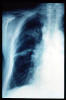

Neumonía basal.